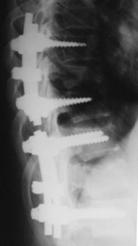

При сгибательно-дистракционном повреждении выполняли фиксацию поврежденного позвоночно-двигательного сегмента с частичной резекцией дугоотростчатых суставов с целью лучшей адаптации задних костных структур при репозиции и задний локальный спондилодез (рис. 15).

Рис. 15. Рентгенограммы пациентки А. 17 лет. Сгибательно-дистракционное повреждение Th12.

А – КТ до операции; Б – через 4 года после задней непрямой репозиции, транспедикулярной фиксации и заднего спондилодеза |